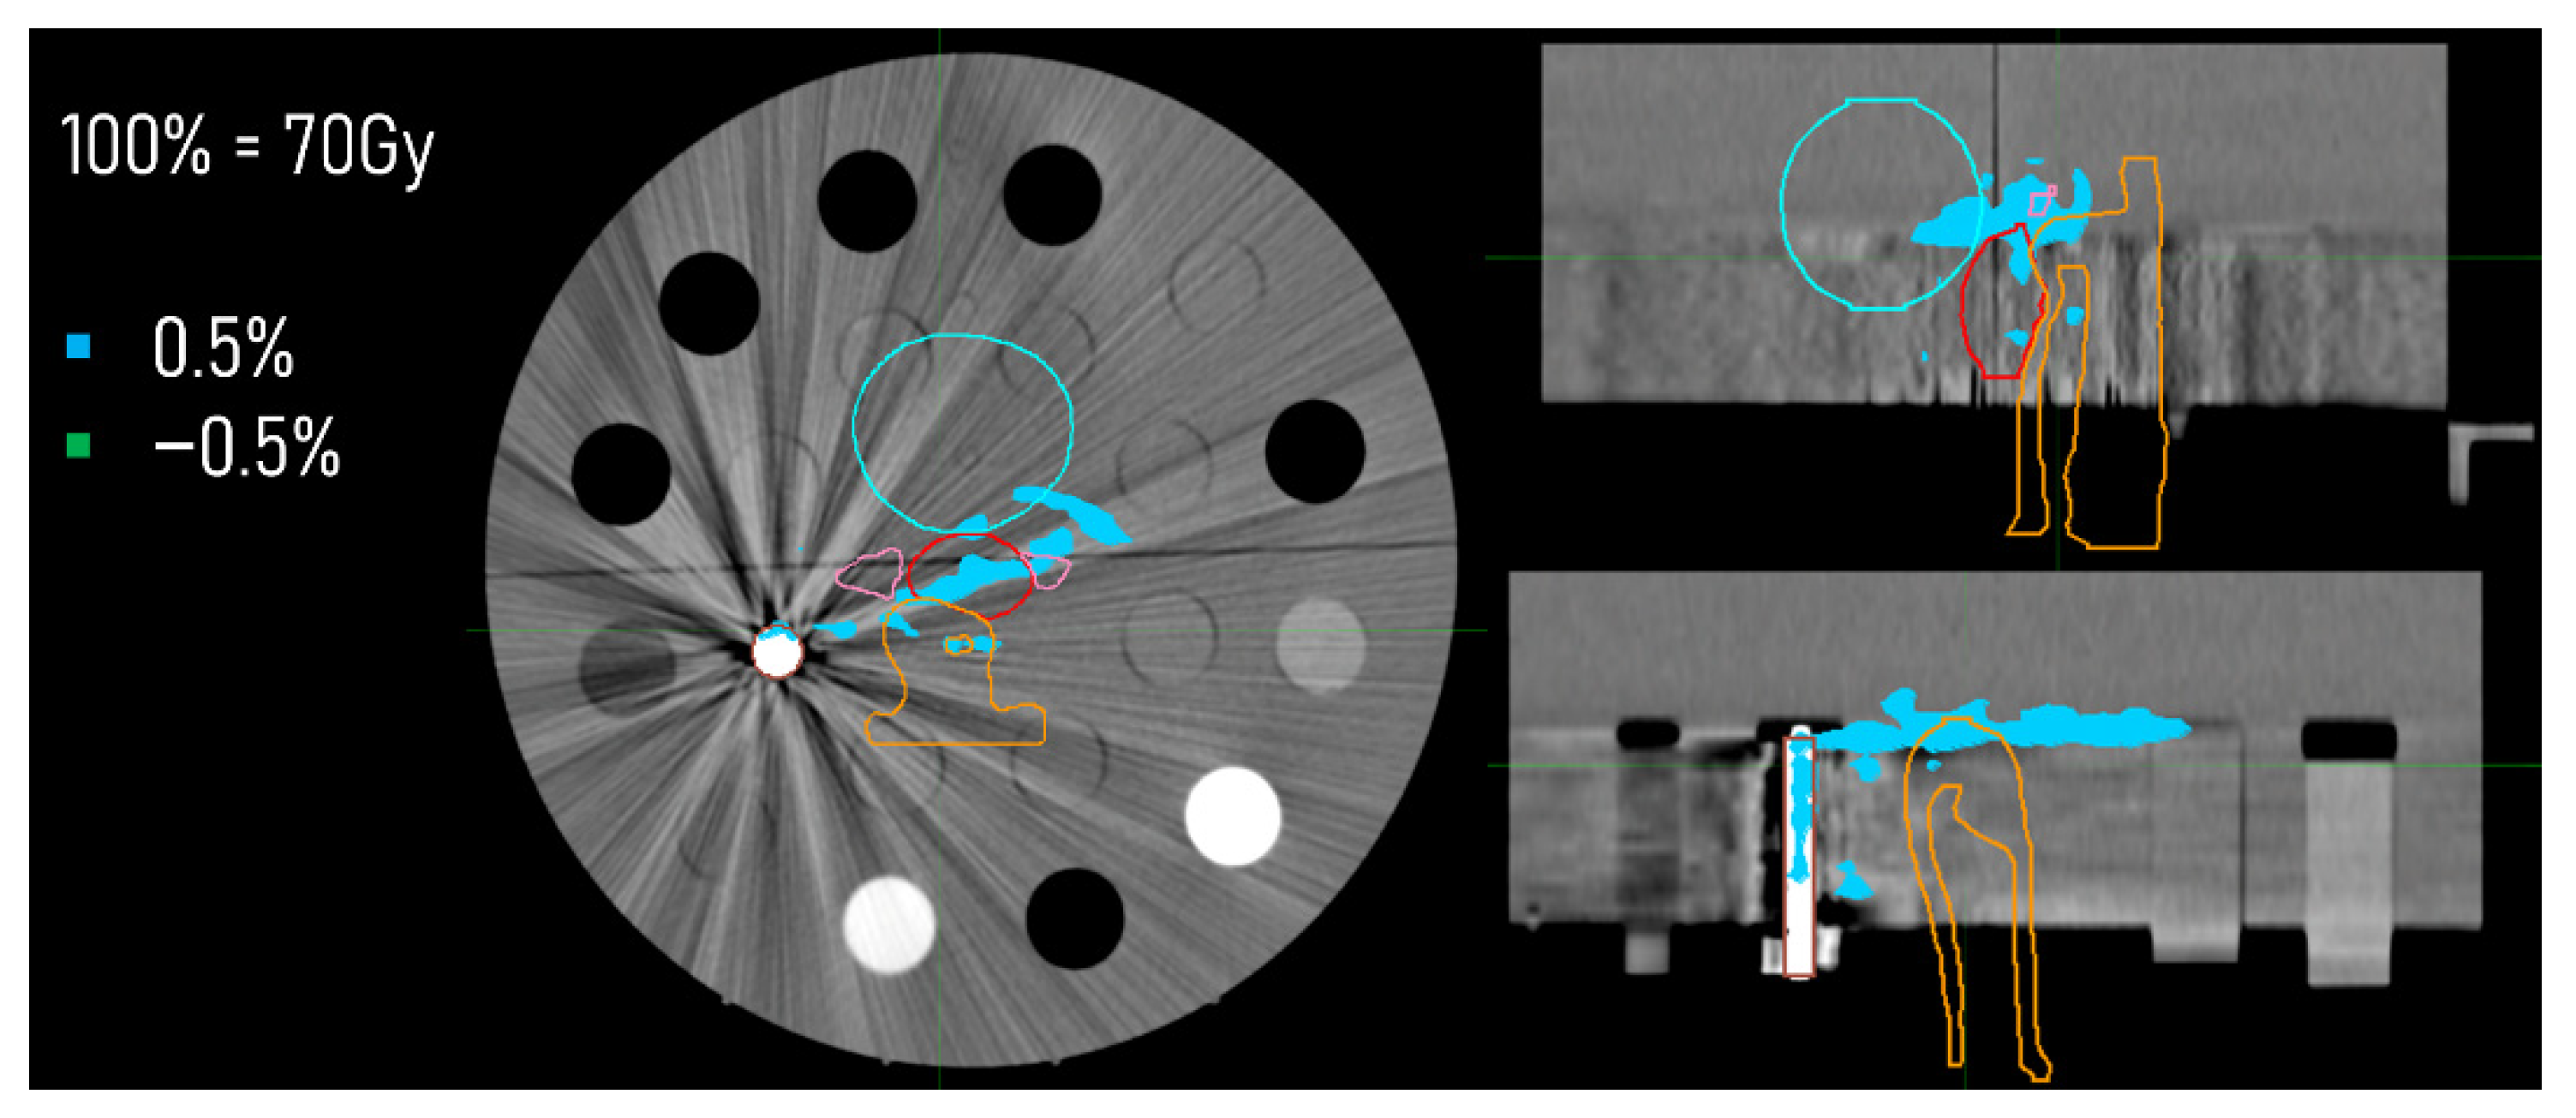

3.3. Dose Distributions